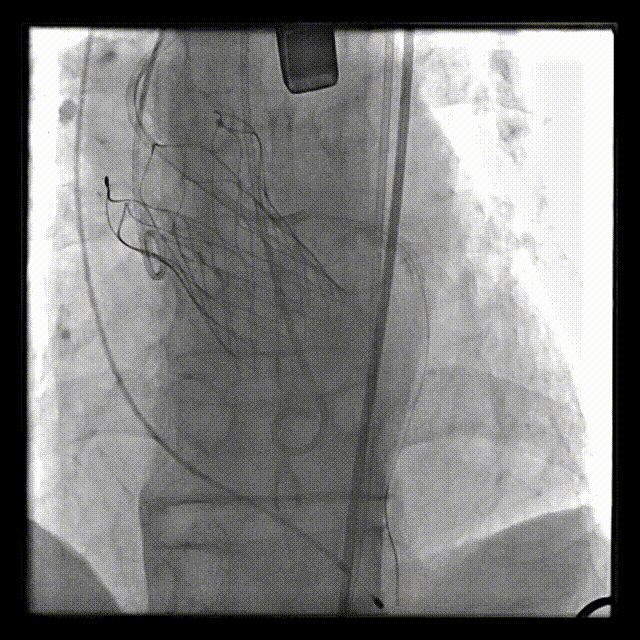

主动脉根部造影示重度主动脉瓣反流